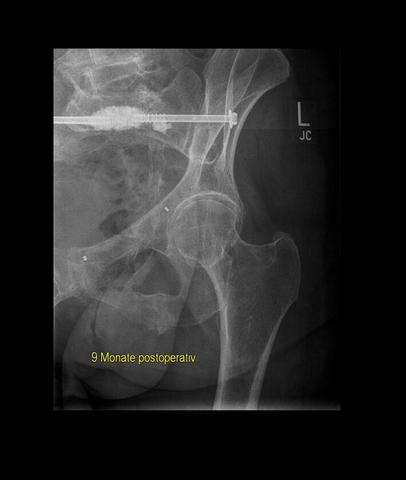

Bei einem vollständigen oder instabilen Beckenbruch ist in den meisten Fällen eine Operation notwendig. Dabei werden die unterbrochenen Beckenteile miteinander verschraubt, um eine stabile Heilung zu ermöglichen. Nach dem Eingriff müssen die Patienten für einige Wochen das Bett hüten. Bei komplizierten oder mehrfachen Beckenbrüchen kann es unter Umständen Monate dauern, bis der Patient seine Beine wieder belasten darf. Die genaue Verweildauer im Krankenhaus richtet sich nach der Schwere der Verletzung und kann mehrere Wochen betragen.